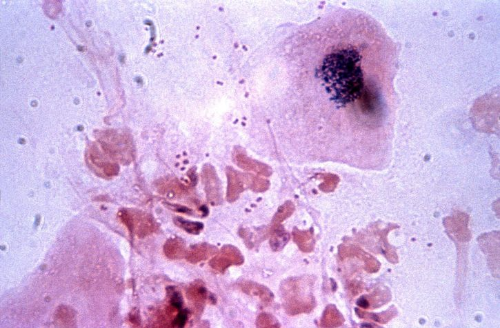

백혈구 수치가 낮아지게 되면 면역기능 또한 낮아지게 되고 감염 위험이 증가하게 되요. 자칫 생명을 위협하는 상황이 오게 될 수도 있다는 말인데요. 이렇게 백혈구 수치 낮으면 그에 대한 원인을 많이 찾아볼 수 있는데 인체면역결핍바이러스나 골수질환, 비장 질환이나 간 질환, 호중구감소증, 자가면역질환과 같은 질병으로부터 그 원인을 찾을 수 있기도 합니다.

인체면역결핍바이러스가 그 원인이라고 하면 다들 아시는 에이즈에 걸리게 될수도 있는데, 세균과 곰팡이등에 의한 미생물로 인해서 치명적으로 노출되게 될 수 있어요. 그리고 자가면역질환은 외부에서 들어오는 침입자로부터 우리의 신체를 지켜야하는 면역세포가 오히려 자신의 몸을 공격하게 되는 질환이라고 보시면 됩니다.

또한 림프종의 경우에는 몸의 면역체계를 구성하고 있는 림프조직에 종양이 발생하게 되는 것으로 다발성으로 나타나는 경우도 습니다.

호중구 감소증은 세균 혹은 박테리아가 우리의 몸 안으로 침입을 하게 되었을때 방어하는 첫번째 방어선이라고 생각하면 되는데 이러한 호중구가 비정상적으로 줄어드는 것을 호중구 감소증이라고 합니다.